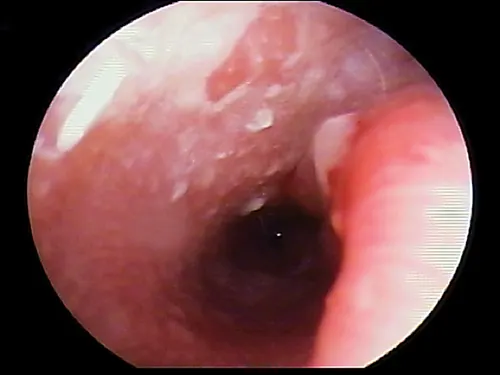

In some dogs, the pars flaccida of the eardrum may be bulging from fluid pressure in the middle ear behind it (Figure 16) and may obscure visualization of the pars tensa. Some have suggested that this enlargement may be caused by degranulation of mast cells and resultant edema from atopic dermatitis.7,8 This condition is frequently mistaken for a mass in the external canal and should be closely evaluated.

Otoscopic image of domed eardrum with hair and yellow exudate visible in internal ear canal.

FIGURE 16

Bulging eardrum caused by increased fluid pressure in the middle ear

In the Cavalier King Charles spaniel, a condition called primary secretory otitis media can cause bulging of the eardrum resulting from the failure of mucoid drainage from the tympanic bulla through the auditory tube.